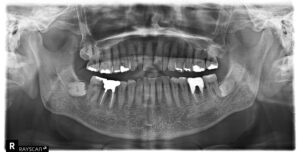

・レントゲン写真の撮影

歯ぐきに隠れて目視できない歯槽骨の吸収状態、歯石が深く付着している場所、そして虫歯の有無を確認します。これにより、歯周病の**進行度(ステージ)**を正確に診断し、P②以降の治療戦略を立てるための必須情報となります。 実際のレントゲン写真です。※患者様の許可を得て記載しております

※患者様の許可を得て記載しております。